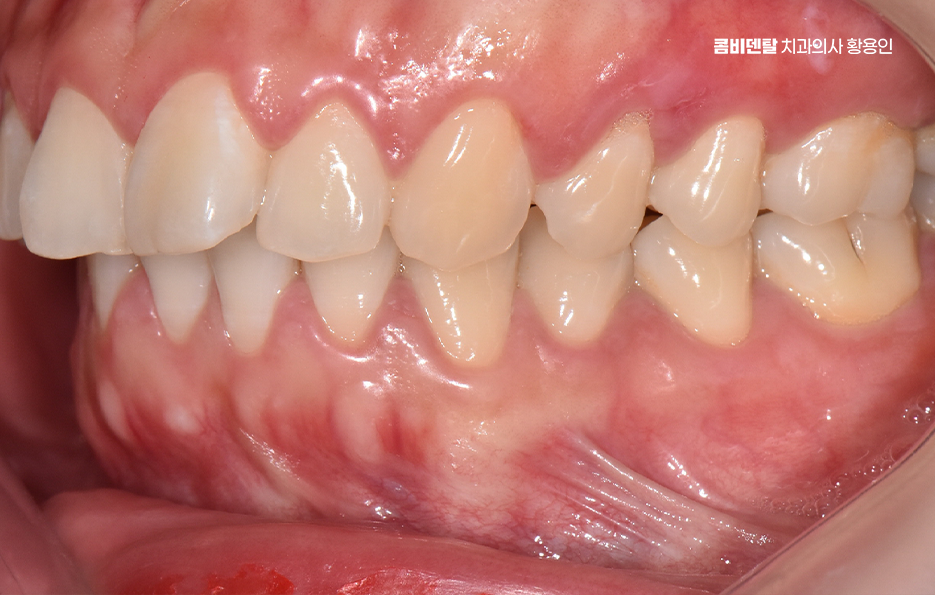

먼저 돌출입이라는 건 치아만 튀어나와 있는 경우도 있지만, 잇몸뼈 자체가 앞으로 튀어나와 있는 골격적인 돌출도 있는데 치아 돌출만 있는 경우는 치아 교정만으로도 비교적 간단하게 개선이 가능하지만 골격적인 돌출이 심한 경우에는 치아교정만으로는 한계가 있어서 수술교정을 병행해야 하는 경우도 있었어요.

하지만 대부분의 경우는 발치교정만으로도 충분히 개선이 가능하며 돌출입이 있을 때는 입술이 자연스럽게 다물어지지 않아서 턱 주변에 불필요한 힘이 들어가고, 표정이 어색해 보이기 쉬운데 이런 불균형을 치아 위치를 조절함으로써 완화시킬 수 있는 거예요.

돌출입 팔자주름 교정 치아를 어떻게 움직이느냐에 따라 얼굴 인상이 달라지는 것인데 돌출입 교정은 일반적으로 소구치 네 개를 발치한 후, 앞니를 뒤쪽으로 밀어넣고 악궁을 재배열하는 방식으로 진행되며 앞니가 뒤로 이동하고 자연스럽게 입술이 들어가게 되고, 입술 돌출도가 줄어들면서 얼굴이 전반적으로 부드럽고 조화로운 느낌으로 바뀔 수 있어요

옆모습에서 입이 덜 나와 보이고, 턱선이 또렷해지는 것도 이런 원리에서 비롯되며 치아 배열 자체는 물론이고, 입술과 턱 근육의 균형이 맞춰지기 때문에 얼굴 인상이 부드럽고 안정적으로 바뀌는 거예요.